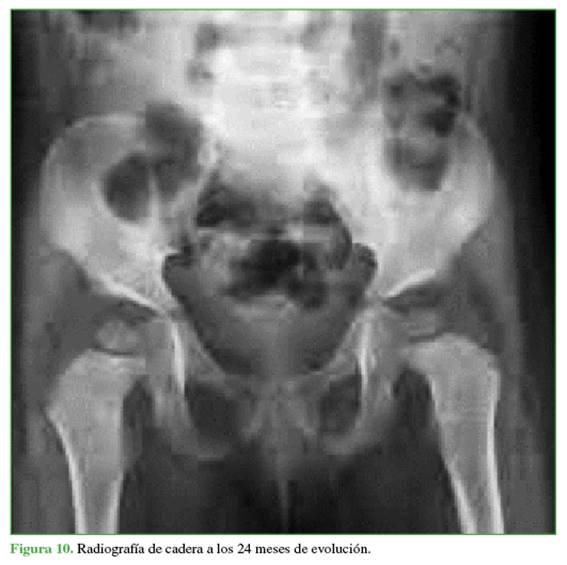

En las Figuras 9 y 10, se muestra la resolución a los 6 y 24 meses del retiro del material.